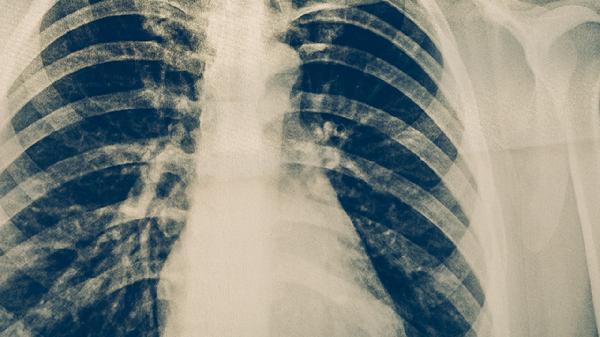

肺結(jié)核的飲食

肺結(jié)核患者可以適量食用高蛋白食物、富含維生素的食物、易消化食物、含鐵食物以及滋陰潤肺的食物。肺結(jié)核是由結(jié)核分枝桿菌引起的慢性傳染病,合理飲食有助于增強(qiáng)免疫力、促進(jìn)病灶修復(fù)。